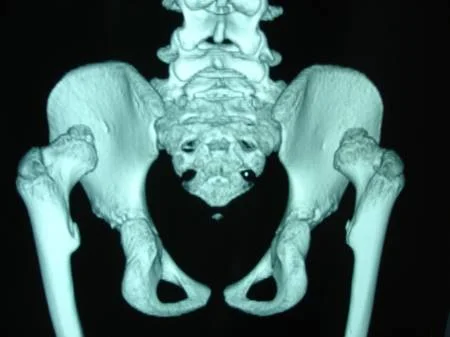

La Displasia del Desarrollo de la Cadera ó Displasia Evolutiva de la Cadera, es un problema dinámico que abarca un amplio espectro de condiciones patológicas, clínicas y radiológicas, que incluyen desde  la cadera luxada, subluxa y la inestable, pasando por la displasia o alteración del desarrollo acetabular o de la cabeza del fémur. Ver más.